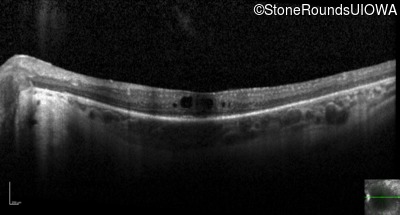

Optical Coherence Tomography - Right - 20/60 -1

Exemplar / OCT Stack